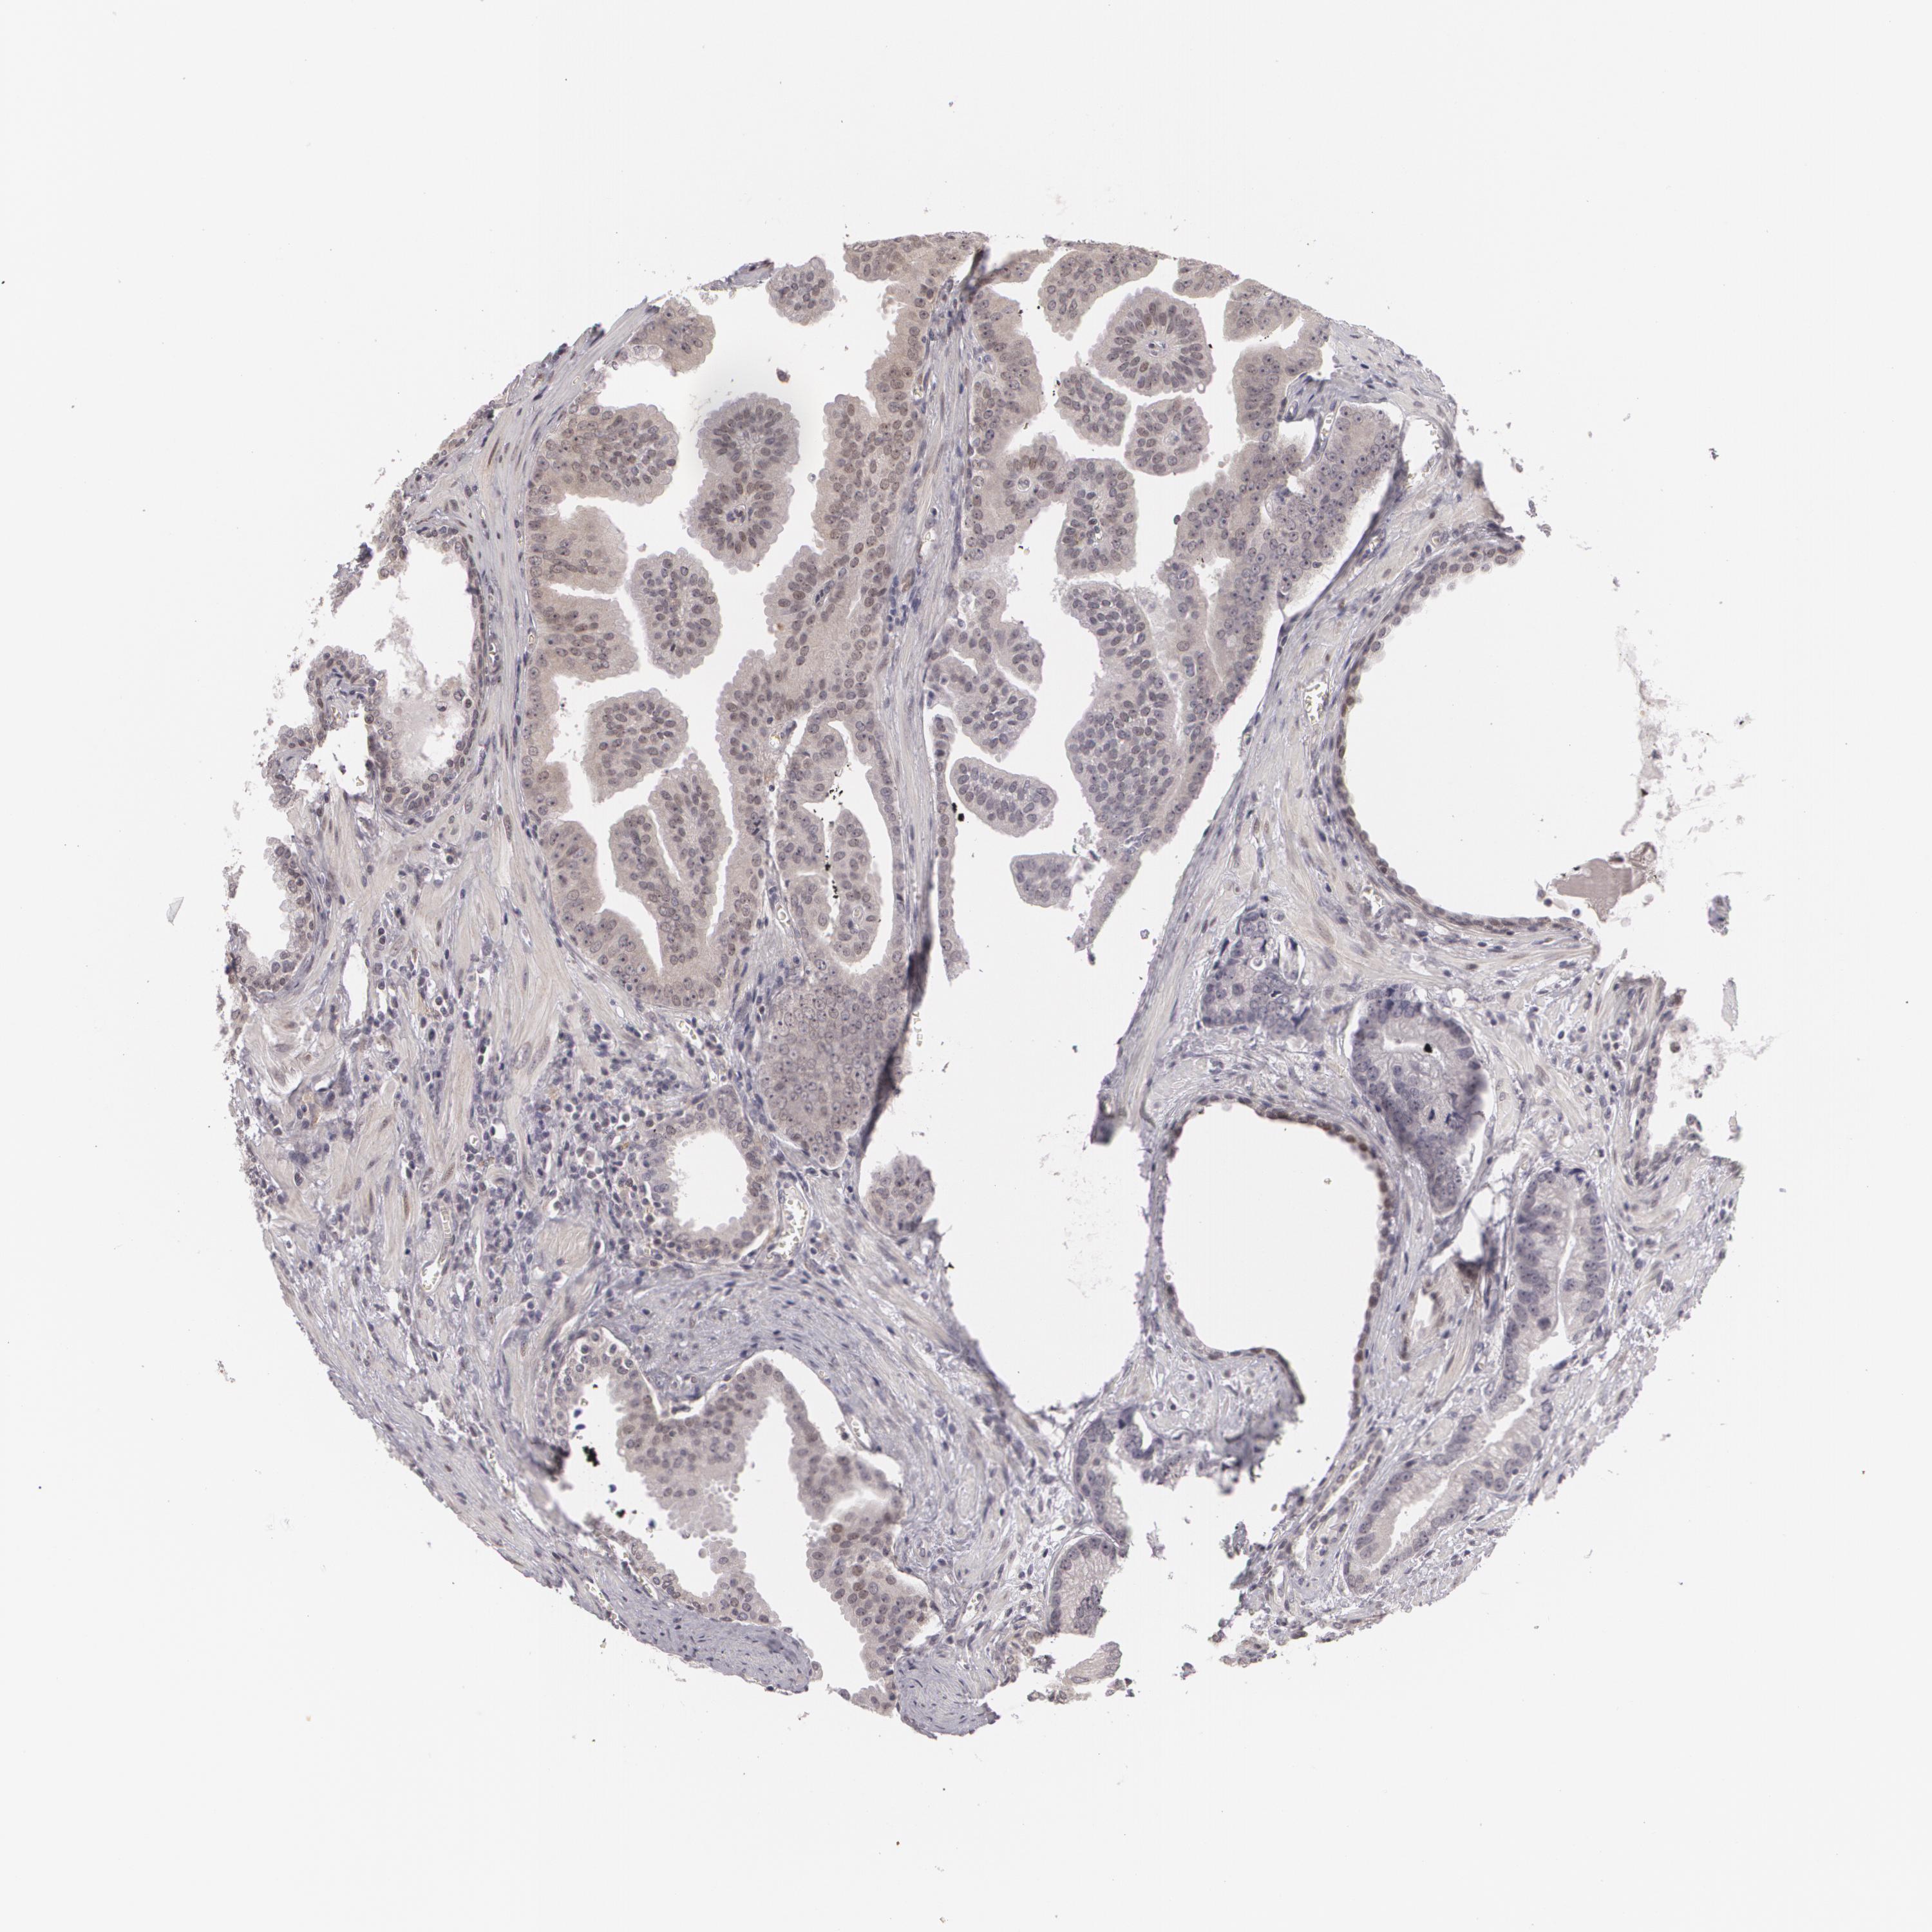

PROSTATE CANCER - Protein expressioni

A mouse-over function shows sample information and annotation data. Click on an image to view it in a full screen mode. Samples can be filtered based on level of antibody staining by selecting one or several of the following categories: high, medium, low and not detected. The assay and annotation is described here.

Note that samples used for immunohistochemistry by the Human Protein Atlas do not correspond to samples in the TCGA dataset.

Antibody stainingi

Antibody staining in the annotated cell types in the current human tissue is reported as not detected, low, medium, or high, based on conventional immunohistochemistry profiling in selected tissues. This score is based on the combination of the staining intensity and fraction of stained cells.

Each image is clickable and will lead to virtual microscopy that enables deeper exploration of all samples and also displays staining intensity scores, fraction scores and subcellular localization as well as patient and tissue information for each sample.

Antibody HPA001499

Antibody CAB004540

Staining

High

Medium

Low

Not detected

Intensity

Strong

Moderate

Weak

Negative

Quantity

>75%

75%-25%

<25%

None

Location

Nuclear

Cytoplasmic/membranous

Cytoplasmic/membranous,nuclear

Adenocarcinoma, Medium grade

Adenocarcinoma, High grade

Adenocarcinoma, Low grade